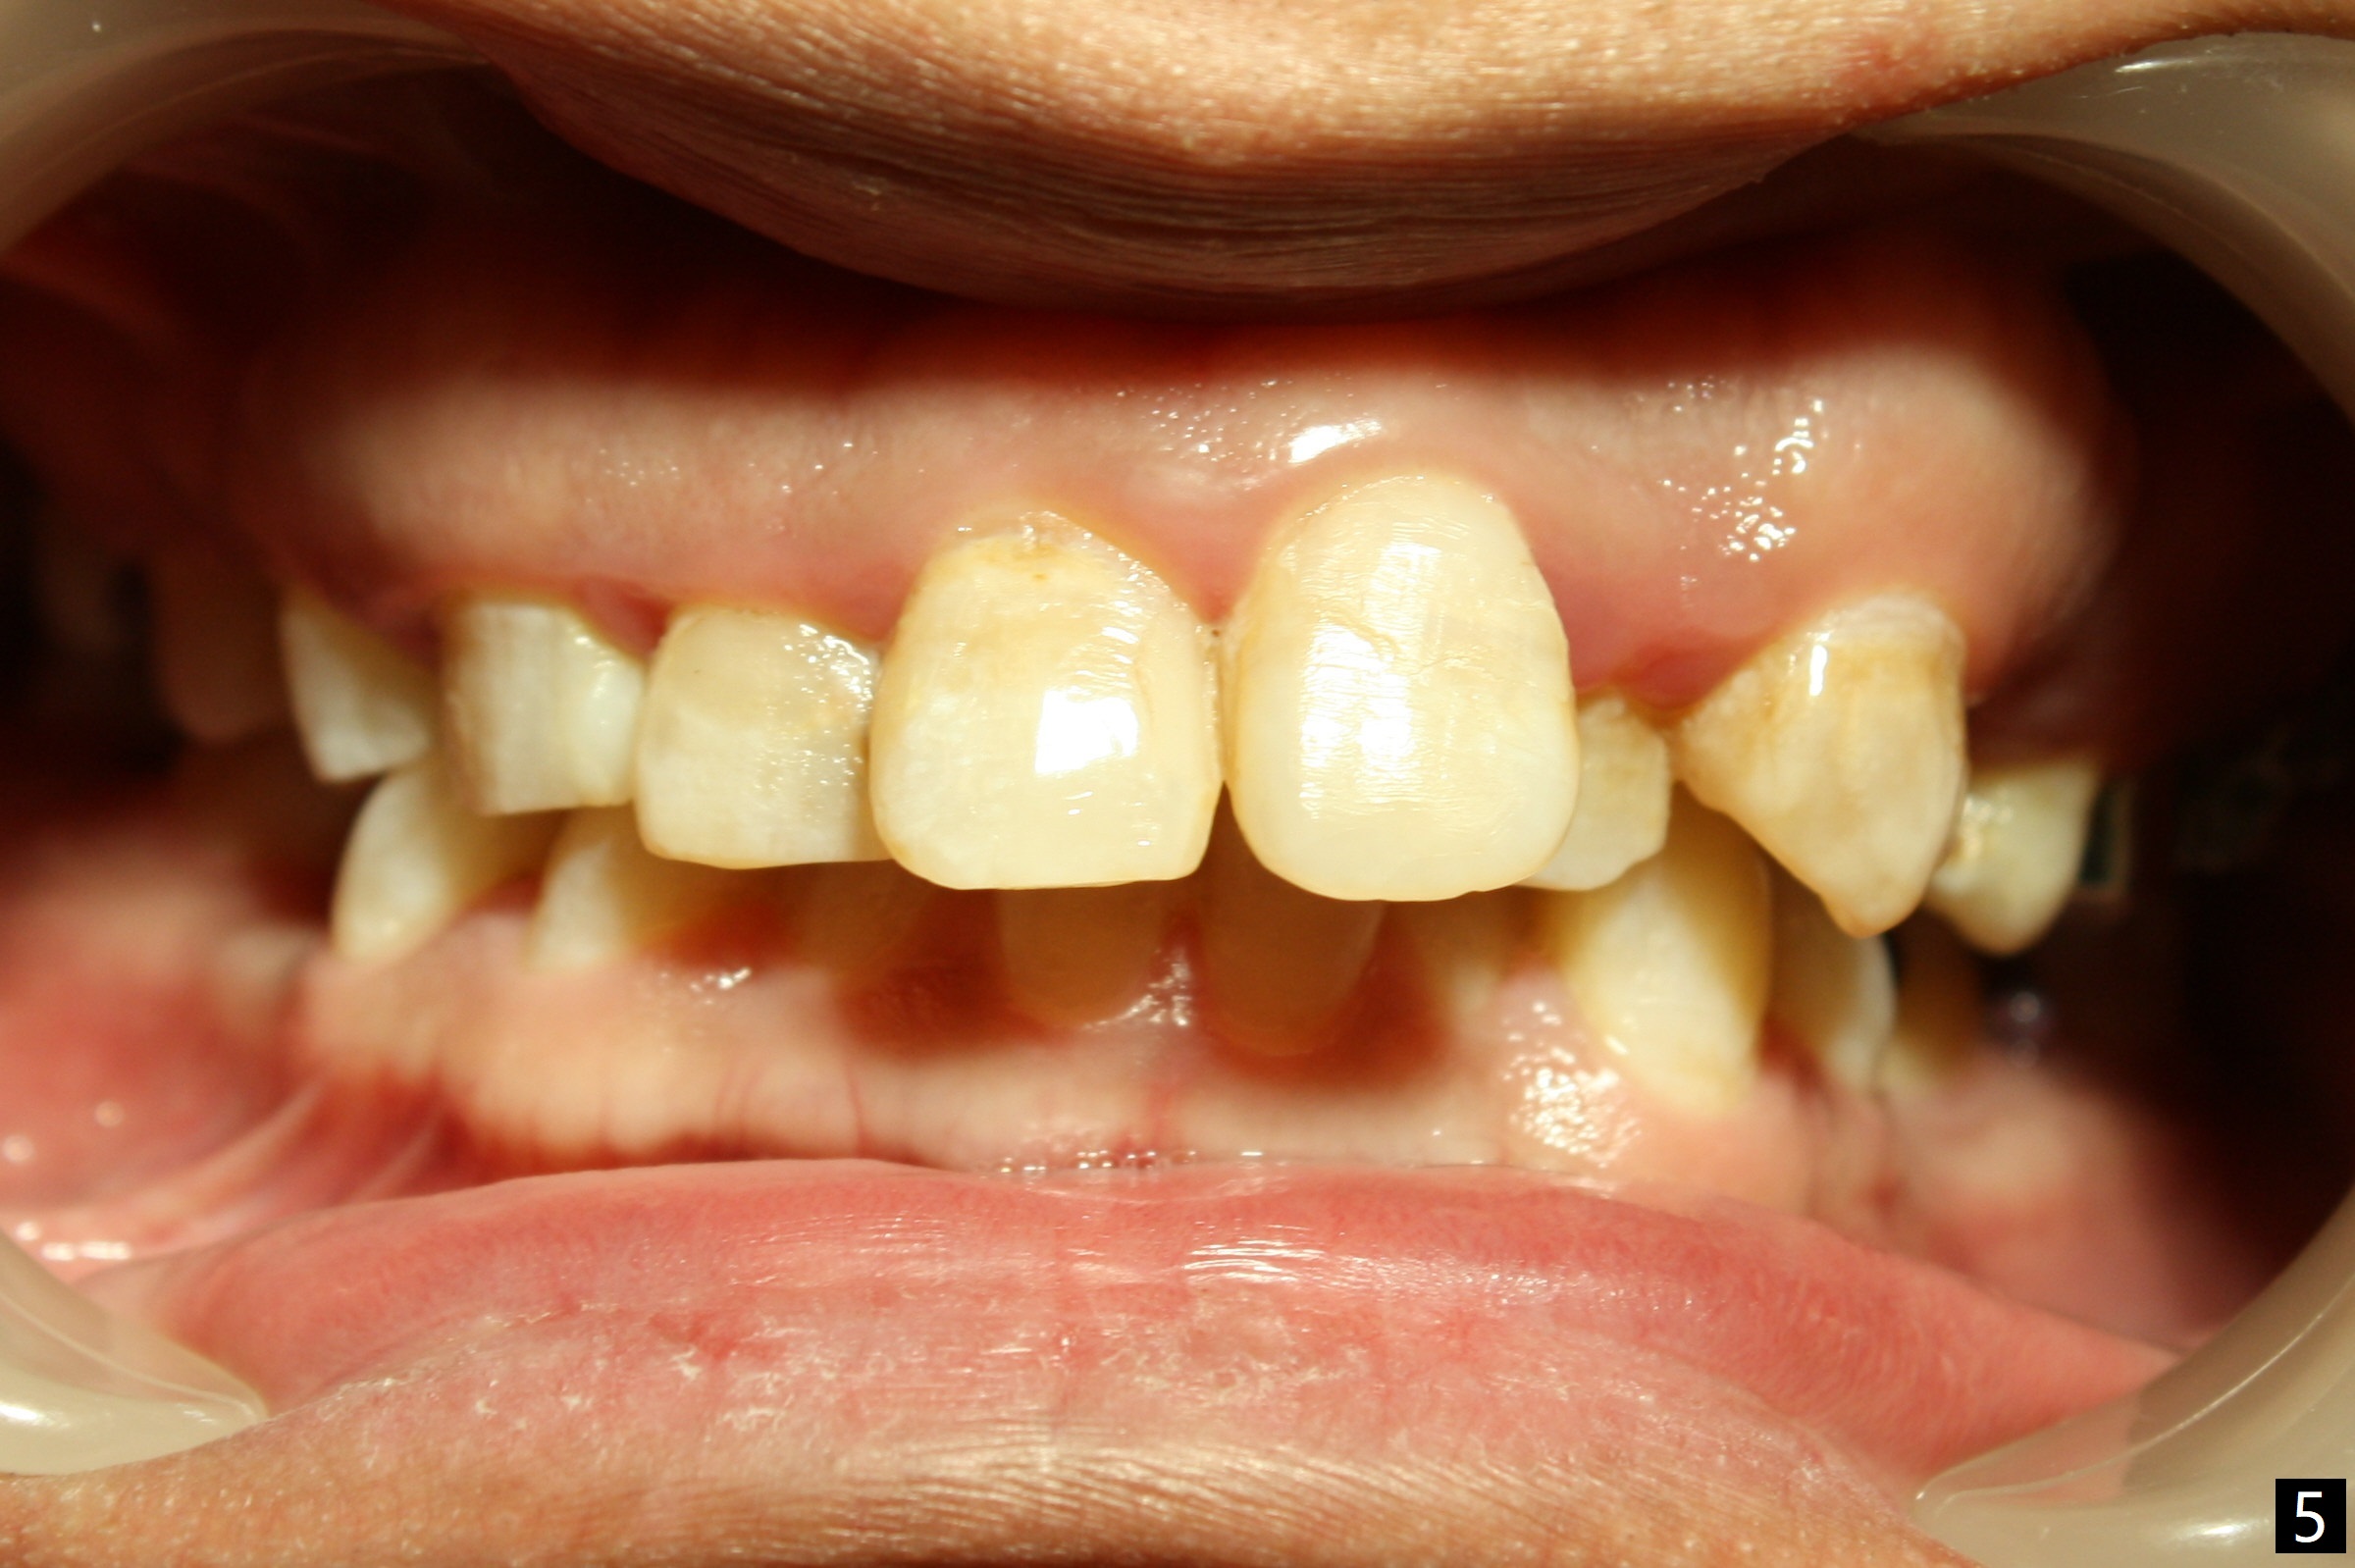

Severe crowding (Fig.1-7) appears to be alleviated especially 2 months after UR5 extraction. Diastemata seem to form mesial and distal to UR2 (Fig.8). Because of severe wear at UR3 (Fig.6), there is no bracket placement differential around it (Fig.8 (14 niti wire)). Lower bands and brackets are placed a week later (Fig.9-11). Because of tight space between LR4 and the opposing tooth (Fig.10), band adhesive is applied to L7 occlusal surface to open the bite (Fig.9). There is an abrupt kink of 12 niti wire between LL4 and 6 (Fig.11). The latter does not improve much in a month; the wires remain the same (Fig.12). For LL2, LR4 has been retracted for ~ 1 month (Fig.13). There is mild tension when 18 ss wire is inserted between LL4 and 6 five point five months post banding (Fig.14). UR4 has been distalized for a month using buccal power chains x3 resulting in rotation; to counter the rotation, a lingual button is placed with power chain x3 lingual and x2 buccal (Fig.15). With space gaining, it is time to finish definitive filling (Fig.16 *). Next visit check midlines, overjet, interdigitation, and molar classification. R4s distalize, but associate with rotation because of power chains buccal and lingual 8 months post banding (Fig.17,18). With the use of the same wires, power chains are applied lingual to continue distalization and rotation correction (Fig.20,21). Lingual buttons are placed at L2s buccalization (Fig.19) and mesialization (Fig.22,23). It appears that space should be created distal to LR3. That is that the lower anterior teeth should be shifted to the right, although it may be not appropriate for the midline.